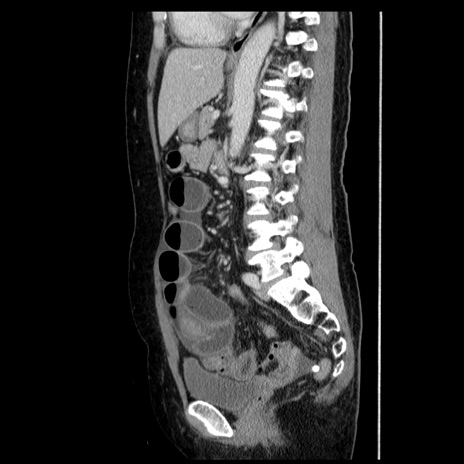

症例6(矢状断像)

横断像